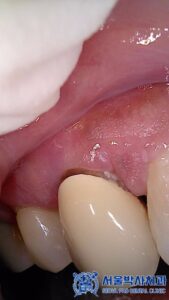

또한 추가적으로

환자분의 앞니 부분에서

치경부 마모가 진행된 것이

확인되었습니다.

치경부 마모는

잇몸 부위 치아가 깎이는 현상으로,

시간이 지나면 시린 증상이

발생할 수 있습니다.

이에 따라,

치경부 레진 치료를 진행하여

마모된 부분을 메꾸어

치아를 보호해 드렸습니다.